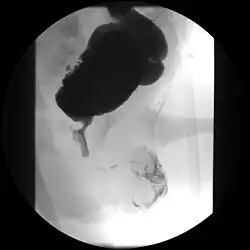

Válvula de uretra posterior

Válvula de uretra posterior (VUP) é uma desordem do desenvolvimento do sistema geniturinário que cursa com obstrução da uretra. A válvula de uretra posterior são folhetos teciduais que se formam na região posterior da uretra masculina durante o crescimento intrauterino. É a causa mais comum de obstrução uretral grave em crianças do sexo masculino. Esta condição apresenta variados graus de apresentação, sendo que os casos mais graves podem apresentar displasia renal e hipoplasia renal devido ao pequeno volume de líquido amniótico durante a gestação.